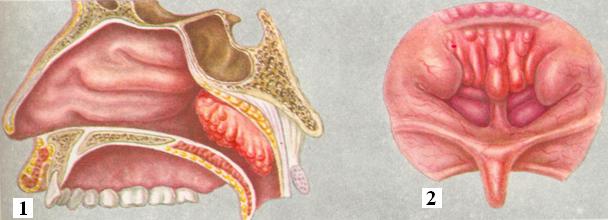

АденоидыАденоиды (греческое aden — железа и eidos — вид; синонимы: аденоидные вегетации, аденоидные разращения) — патологическая гипертрофия «третьей», или глоточной (носоглоточной), миндалины (tonsilla pharyngeal находящейся в своде носоглотки. Эта миндалина вместе с язычной и небными миндалинами входит в состав лимфаденоидного глоточного «кольца». Толщина глоточной миндалины в среднем 5—7 мм, ширина 20 мм и длина 25 мм. Щели между валиками имеют вид прямолинейных или по периферии дугообразно изогнутых бороздок, параллельных друг другу или сходящихся кзади. Наиболее глубокая, располагающаяся по средней линии бороздка заканчивается кзади вдавлением, носящим название глоточной сумки (bursa pharyngea). Глоточная миндалина развита только в детском возрасте, приблизительно с 12 лет она начинает уменьшаться в размерах. К 16—20 годам обычно сохраняются лишь небольшие остатки лимфаденоидной ткани, а у взрослых обычно наступает полная атрофия ее. Глоточная миндалина, упоминание о которой имеется еще в труде Санторини (G. D. Santorini), более подробно описана Лушкой (Н. Luschka), по имени которого ее нередко называют миндалиной Лушки. Н. И. Пирогов указывал на то, что между сводом глотки и основной частью затылочной кости имеется скопление слизистых фолликулов и что в них нужно искать первичный очаг заглоточных нарывов. У больного аденоидами впервые обнаружил Чермак (J. N. Gzermak, 1860) при помощи предложенного им метода задней риноскопии. Но наиболее полное клиническое описание на основании 48 наблюдений было дано датским врачом Мейером (Н. W. Meyer) в 1873 г. Симптоматология аденоидных разращений существенно обогатилась после того, как была доказана связь между заболеваниями носа и общими нарушениями в организме. Исследованиями вирусологов было выявлено, что глоточная и небные миндалины являются резервуаром как латентных, так и эпидемических аденовирусов, где они создают постоянный очаг инфицирования и сенсибилизации, периодически вызывая не только обострения хронического аденоидита, но и повторные острые респираторные заболевания и обострения бронхо-легочных процессов. Аденоидные разращения имеют большое значение в патологии верхних дыхательных путей и органа слуха. Наличие аденоидов вызывает не только местные расстройства в виде затруднения носового дыхания, нарушений слуха, изменения голоса, но часто неблагоприятно отражается на общем состоянии организма. Аденоиды образуются в результате патологического разрастания лимфаденоидной ткани глоточной миндалины (рис. 1). При гипертрофии глоточная миндалина распространяется кпереди до хоан и сошника, кзади до глоточного бугорка (tuberculum pharyngeum), в стороны — до глоточных карманов (розенмюллеровых ямок) и раструбов слуховых (евстахиевых) труб. Размеры аденоидов (несколько условно) определяют с помощью задней риноскопии (рис. 2). Различают три степени разрастания глоточных миндалин: I степень — аденоиды прикрывают верхнюю часть сошника, II степень — верхние две трети сошника и III степень — большие аденоиды, прикрывающие полностью или почти полностью сошник. Аденоиды наблюдаются одинаково часто у детей обоего пола обычно в возрасте от 3 до 10 лет, но они встречаются также как в первые месяцы и годы жизни, так и после полового созревания и (как исключение) в пожилом и даже старческом возрасте. Среди амбулаторных больных (при совместном приеме взрослых и детей) процент страдающих аденоиды доходит до 6—7; в детских амбулаториях цифра эта значительно выше. Этиология.Причины гипертрофии носоглоточной миндалины разнообразны. Часто быстрый рост аденоидов является результатом детских инфекционных заболеваний (корь, коклюш, скарлатина, дифтерия, грипп и другие) вызывающих воспалительную реакцию слизистой оболочки полости носа и лимфаденоидной ткани носоглотки. Неблагоприятные бытовые условия (сырые, темные и плохо проветриваемые помещения, качественно и количественно недостаточное питание и так далее) снижают защитные функции организма, часто ведут к острым и хроническим воспалениям верхних дыхательных путей, предрасполагающим к развитию аденоидов. |

Рис. 1. | ||